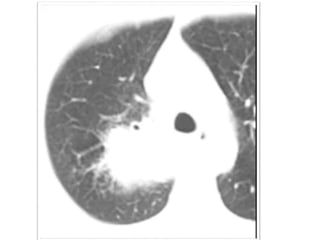

Punción Guiada por TAC

• Para nódulos periféricos

• A 2 cm de la pleura

• S 80-95% E 50-88%

• VPP 98,6% VPN 96,6%

• Complicaciones: NTX

• Cuando el nódulo es < 2 cm baja la

sensibilidad de este procedimiento.

Punción Guiada porTAC • Para nódulos periféricos • A 2 cm de la pleura • S 80-95% E 50-88% • VPP 98,6% VPN 96,6% • Complicaciones: NTX • Cuando el nódulo es < 2 cm baja la sensibilidad de este procedimiento.